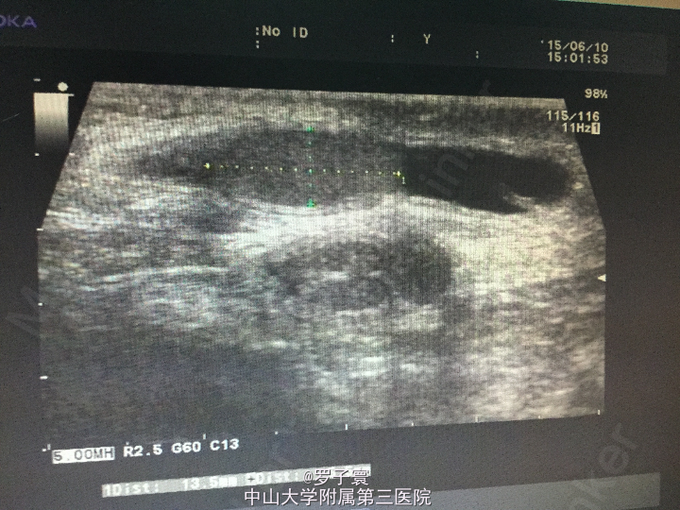

查体:阴茎呈男童外观,包茎,左侧阴囊空虚,未触及任何内容物,左侧腹股沟可触及睾丸样团块,质地软,大小1.4*0.6cm,无触痛,无粘连,站立活动后右侧阴囊可触及质软肿物,透过试验阳性,可扪及右侧睾丸,大小约1.5*0.8cm,触诊质地软,表面光滑,无硬结,无压痛,附睾、精索触诊不满意。生殖系彩超(我院,2015-06-10):双侧阴囊内睾丸缺如;双侧腹股沟部隐睾(左侧活动度大);右侧睾丸鞘膜积液。